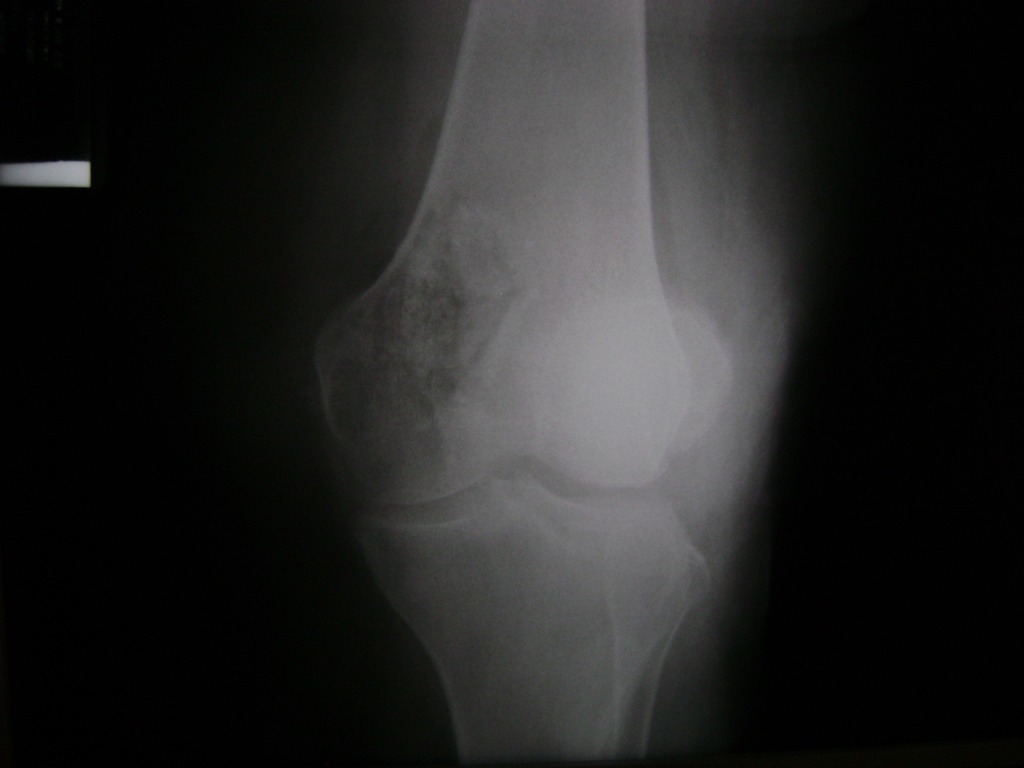

La artroscopia de rodilla es un cirugía en el cual la estructura interna de la articulación es examinada ya sea para realizar un diagnostico o para realizar un tratamiento, este procedimiento se realiza utilizando un instrumento parecido a un pequeño tubo llamado artroscopio.

La artroscopia se popularizo en 1960 y hoy en día es muy común en todo el mundo. Típicamente, es realizada por cirujanos ortopédicos de manera ambulatoria. Cuando se realiza de manera ambulatoria los pacientes pueden regresar a casa después de la operación, no se requiere quedarse en hospital.